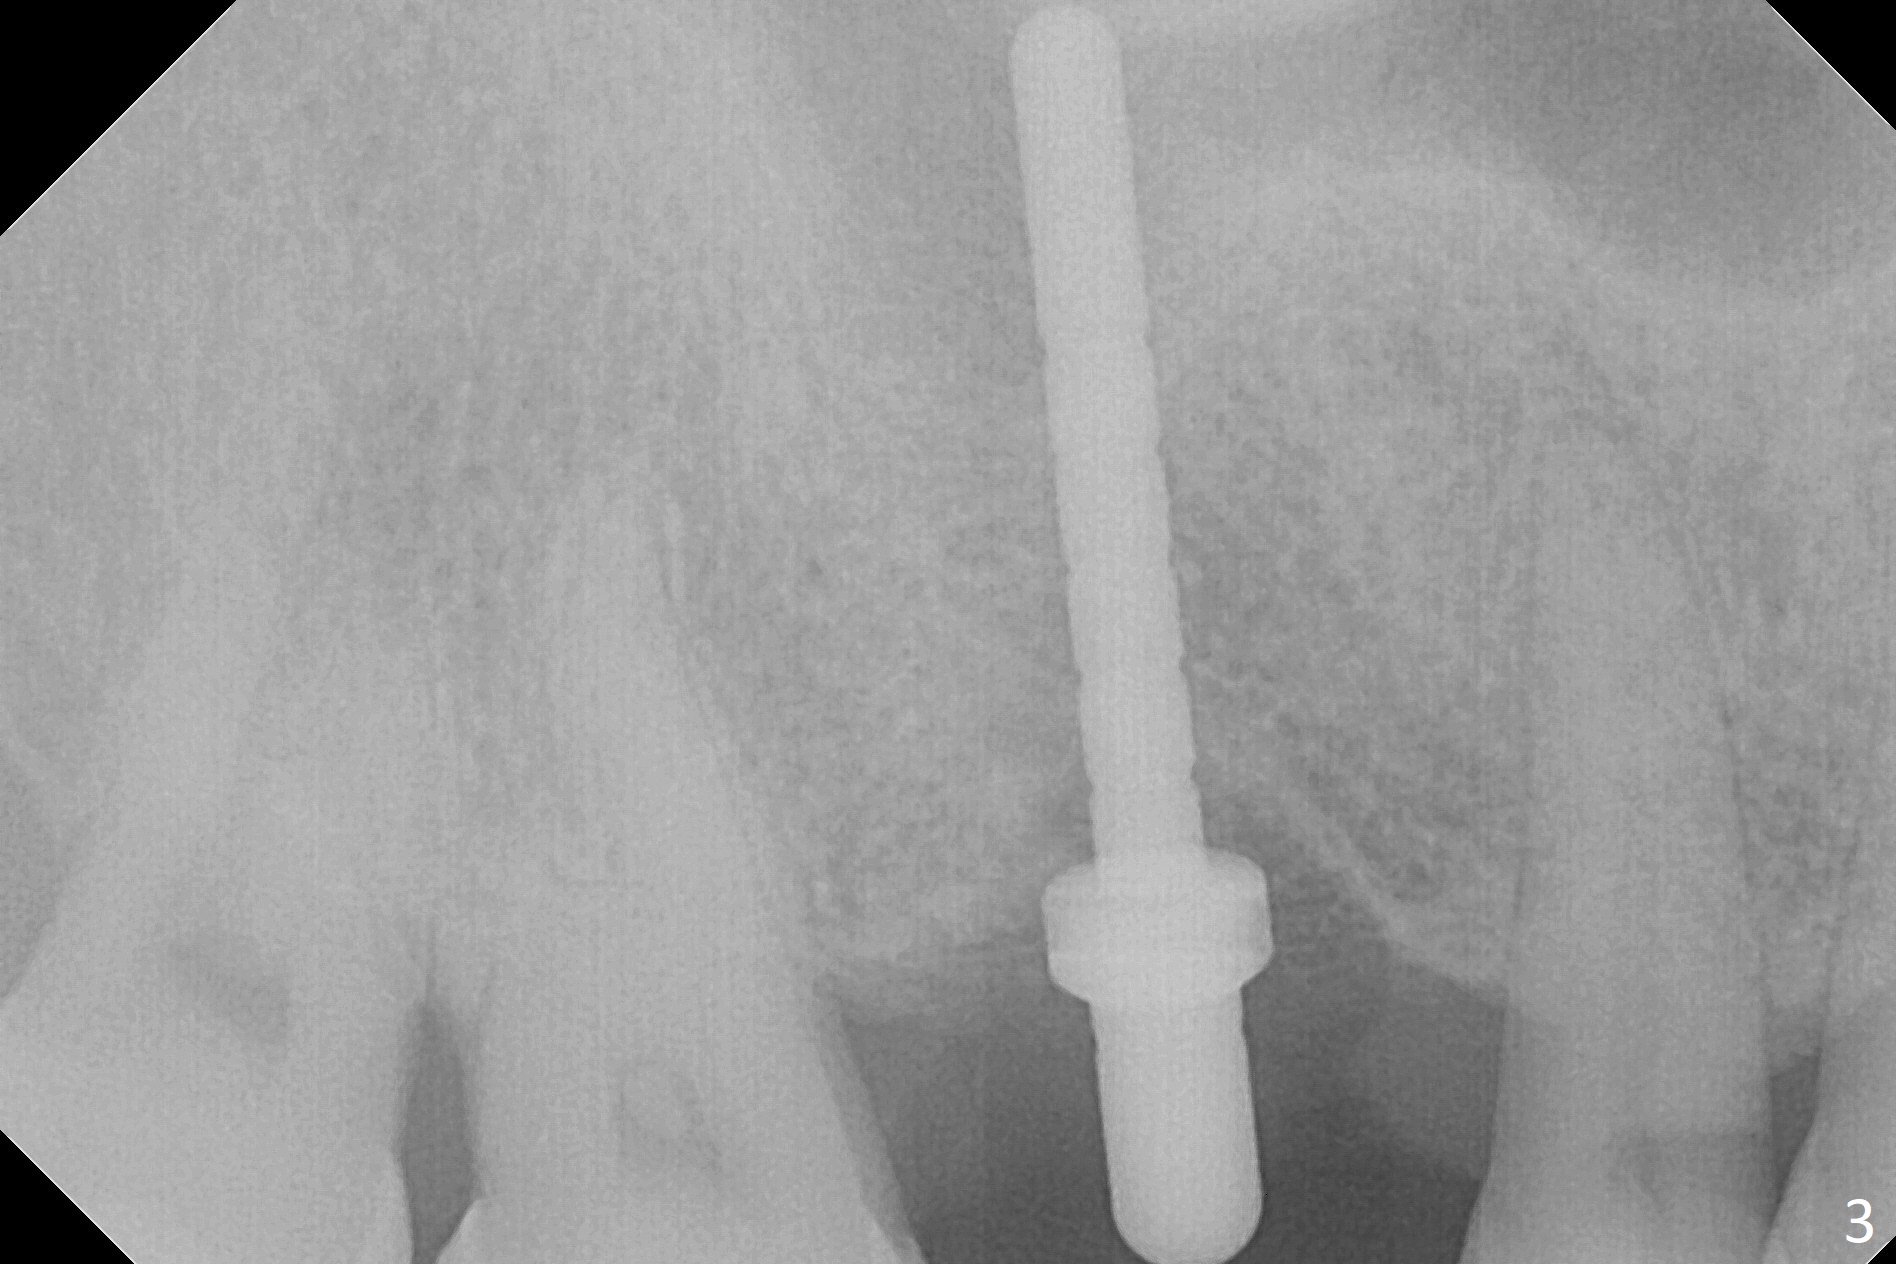

The clearance between the residual roots of the tooth #3 and the abutment at #30 seems to be somewhat limited (Fig.1). The initial osteotomy depth is 10 mm (Fig.2). After moving the osteotomy mesially, the depth increases to 12 mm; a parallel pin is inserted for 16 mm (Fig.3 with sinus membrane perforation). The depth of the rest of the osteotomy is 10 mm with placement of a 5x10 mm implant with >50 Ncm (Fig.4); with insertion of a 6.8x4(3) mm abutment and Vera Graft (*), an immediate provisional is fabricated. Collagen plug is used to seal the gap between the provisional and the gingiva. The abutment dislodges nearly 1 month postop; the wound has healed (Fig.5). A 8.2x5(4) mm healing abutment is placed to keep the soft tissue configurement.